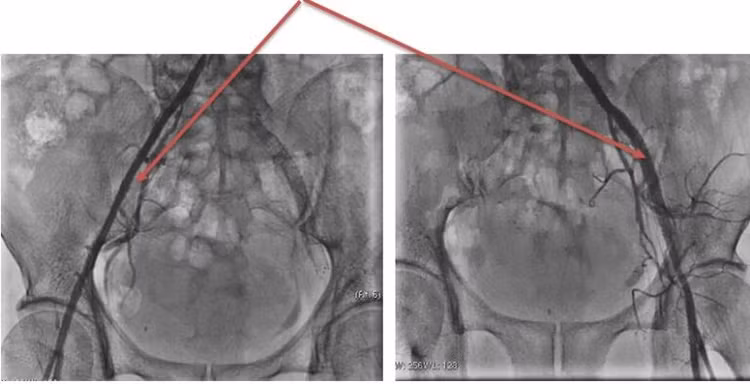

Người bệnh Đ.T.H (sinh năm 1962, Việt Trì) thường xuyên bị đau 2 chân, mỗi lần chỉ đi được tầm 50m, gây khó khăn, bất tiện trong sinh hoạt. Đến khám tại Khoa Can thiệp tim mạch – Trung tâm Tim mạch, người bệnh được chẩn đoán: tắc động mạch chậu 2 bên, đã được chỉ định can thiệp nong bóng, đặt stent động mạch chậu 2 bên. Sau can thiệp 4 ngày, người bệnh đã có thể đi lại bình thường và được ra viện.

Hình ảnh động mạch chậu bị tắc |

| Can thiệp nong bóng động mạch chậu 2 bên |

Động mạch chậu 2 bên thông tốt sau can thiệp |